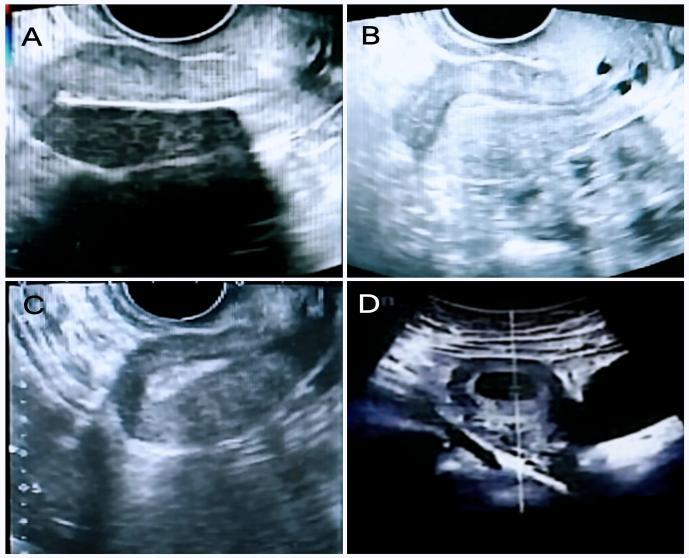

2024年9月24日本院三维超声提示:子宫大小37mm*31mm*40mm,子宫全层厚6.2mm,内膜线居中,局部中断,局部充盈缺损,考虑宫腔粘连可能。

苏州大学附属第一医院三维超声图示

A:PRP宫腔灌注前,内膜3.7mm; B:第一次PRP宫腔灌注后,内膜5.9mm;C:第二次PRP宫腔灌注后,内膜8.6mm; D:PRP结束后4月,确诊宫内孕。